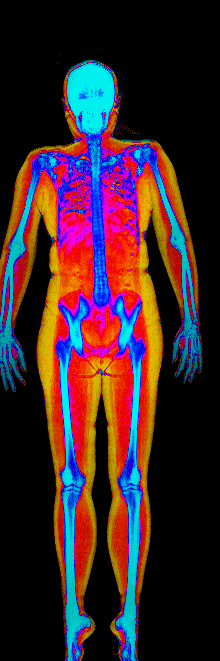

This page features real, anonymized DEXA scan images from BodyStats clients, organized by gender and body fat percentage in 5% increments. DEXA (Dual-Energy X-ray Absorptiometry) is the clinical gold standard for measuring body composition — far more accurate than scales, calipers, or visual estimates.

Each colorized scan shows the distribution of fat tissue (shown in warmer colors) and lean tissue (cooler colors) throughout the body. Compare your own DEXA scan to others in your range, or see what different body fat levels actually look like on a scan.

Female DEXA Scans by Body Fat %

30 to 35% body fat